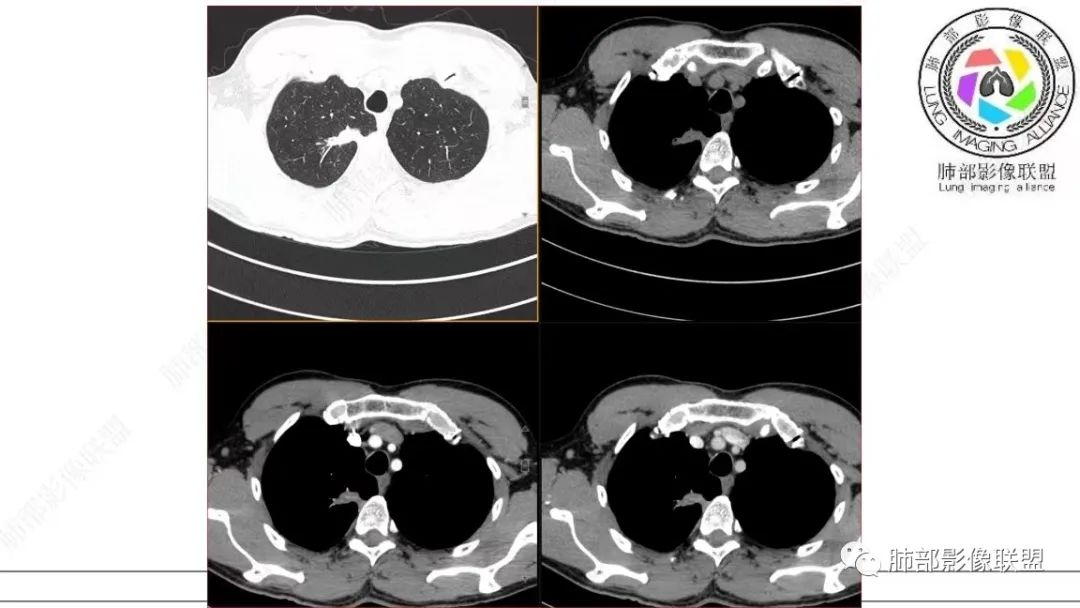

在细支气管腺瘤的文献中,病例较少,没有看到过提到有粘液栓形成的病例描述。细支气管腺瘤的病理要点中,1,可以见到细支气管进入病灶。2.双层细胞。细支气管水平的病变,当然就可以有纤毛,有可以分泌黏液的细胞。在细支气管腺瘤中,形成的粘液,可以弥散在组织间隙,也可以聚集,形成粘液湖。更容易经过细支气管排出,形成空洞。类似于腺癌的空泡。这个病例虽然有延迟强化,收缩力比较强,也有支气管粘液栓,但是比较难解释这么低密度的,有延迟强化的,可疑粘液成分。

这个病例还可以深挖,图像有点少,我感觉部分层面可疑少许磨玻璃。最难鉴别的是结节型黏液腺癌,特别是细支气管腺瘤的收缩力比较弱的时候。这个病例收缩力太强,结节型黏液腺癌不太好解释。结合病理及影像表现,这个病例最终诊断:倾向于细支气管腺瘤、合并一些非特异性的感染、支气管内粘液栓形成。细支气管腺瘤,疑难。实性的细支气管腺瘤,更疑难。再合并感染,难上加难。不讲理的一个病例。

影像诊断

本研究对22处BA的CT影像进行分析,发现以下方面对诊断本病有一定提示意义:①病变部位:本组病例均为周围型病变,多位于下叶,且以胸膜下区为主,与既往研究结果一致。本病细支气管黏膜上皮的起源赋予了其特有的位置分布。②类型:本组GGO14处,实性结节8处。Chang等收集的14处BA中,GGO6处、实性结节8处,与既往研究结果基本一致。此外,部分学者报道呈空洞表现的BA。由此可见,BA的影像表现多样,但主要表现为GGO和实性结节。③大小:本研究显示BA普遍较小,最大径约(0.9±0.7)cm,95%的病变不超过2.0cm。王蓓等、高何等分别纳入8例、15例BA,病灶平均最大径均为1.0cm,与本研究结果一致。④形态:本组BA无论表现为GGO还是实性结节,其形态不规则且边缘毛糙,仅少部分体积较小的BA可呈类圆形或椭圆形,与Kamata等的研究结果相似,推测BA的形态学改变与肿瘤无包膜有关。⑤伴发征象:本研究中BA多伴有中央或外周空泡征、细支气管充气征及血管征,其中以中央空泡征最具特征。刘芳兵等报道2例表现为GGO的BA均伴空泡征;苏雷等报道11例BA中,伴有空泡征8例、血管征10例。可见空泡征和血管征对诊断本病具有重要意义。上述征象与镜下瘤内、瘤周常见细支气管及伴行的厚壁血管有关。此外,胸膜牵拉征、分叶征及毛刺征罕见。⑥强化方式:实性结节表现的BA增强扫描呈延迟性显著强化,部分病灶动脉期可见血管造影征,血管走行自然,未见破坏。血管造影征与镜下病变常见细支气管动脉束穿行相符,此征象也反映了肿瘤位于细支气管周围的定位。⑦随访中病灶保持稳定或缓慢增长。此段内容及病例图片摘自并感谢,黄勇教授、王越老师-细支气管腺瘤的CT表现,发表于中国医学影像杂志。